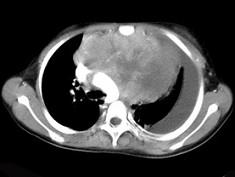

患者胸痛胸闷,CT如图所示,最可能的诊断为 ( )A、表皮样囊肿B、淋巴瘤C、恶性畸胎瘤D、侵袭性胸腺瘤E、良性胸腺瘤

问题 患者胸痛胸闷,CT如图所示,最可能的诊断为 ( )

选项 A、表皮样囊肿 B、淋巴瘤 C、恶性畸胎瘤 D、侵袭性胸腺瘤 E、良性胸腺瘤

答案 D